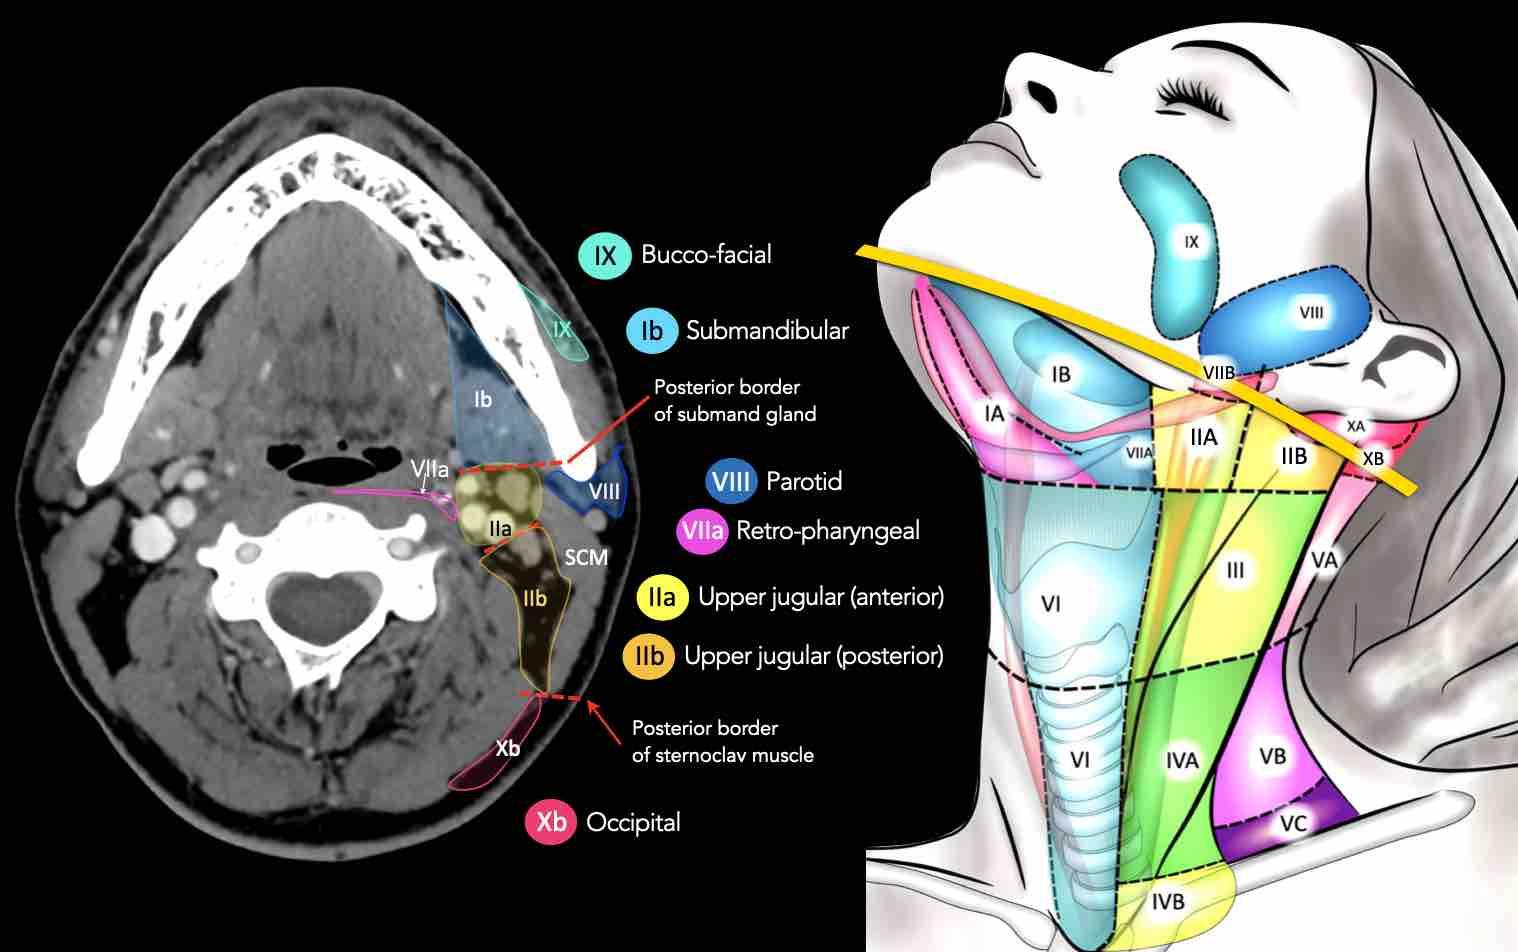

CT Scan Mặt Cắt Ngang (Axial CT)

Các lát cắt CT mặt phẳng ngang tương ứng với hình minh họa tổng quan.

Các lát cắt CT mặt phẳng ngang với hình ảnh chi tiết hơn.

Nhấp vào hình ảnh để phóng to.

II – Tĩnh mạch cảnh trên

Tầng II nhận bạch huyết hướng tâm từ mặt, tuyến mang tai, và các hạch dưới hàm, dưới cằm và sau hầu.

Tầng II cũng nhận trực tiếp các bạch mạch thu thập từ hốc mũi, hầu, thanh quản, ống tai ngoài, tai giữa, và các tuyến dưới lưỡi và dưới hàm [1].

Tầng II có thể được chia thành tầng IIa và tầng IIb bằng cách vẽ một đường tại bờ sau của tĩnh mạch cảnh trong.

Các hạch bạch huyết ở tầng IIa và IIb có nguy cơ chứa di căn từ các ung thư hốc mũi và khoang miệng, vòm hầu, hầu miệng, hạ hầu, thanh quản và các tuyến nước bọt lớn.

Tầng IIb thường liên quan hơn đến các khối u nguyên phát ở hầu miệng hoặc vòm hầu, và ít thường xuyên hơn với các khối u ở khoang miệng, thanh quản hoặc hạ hầu [1].